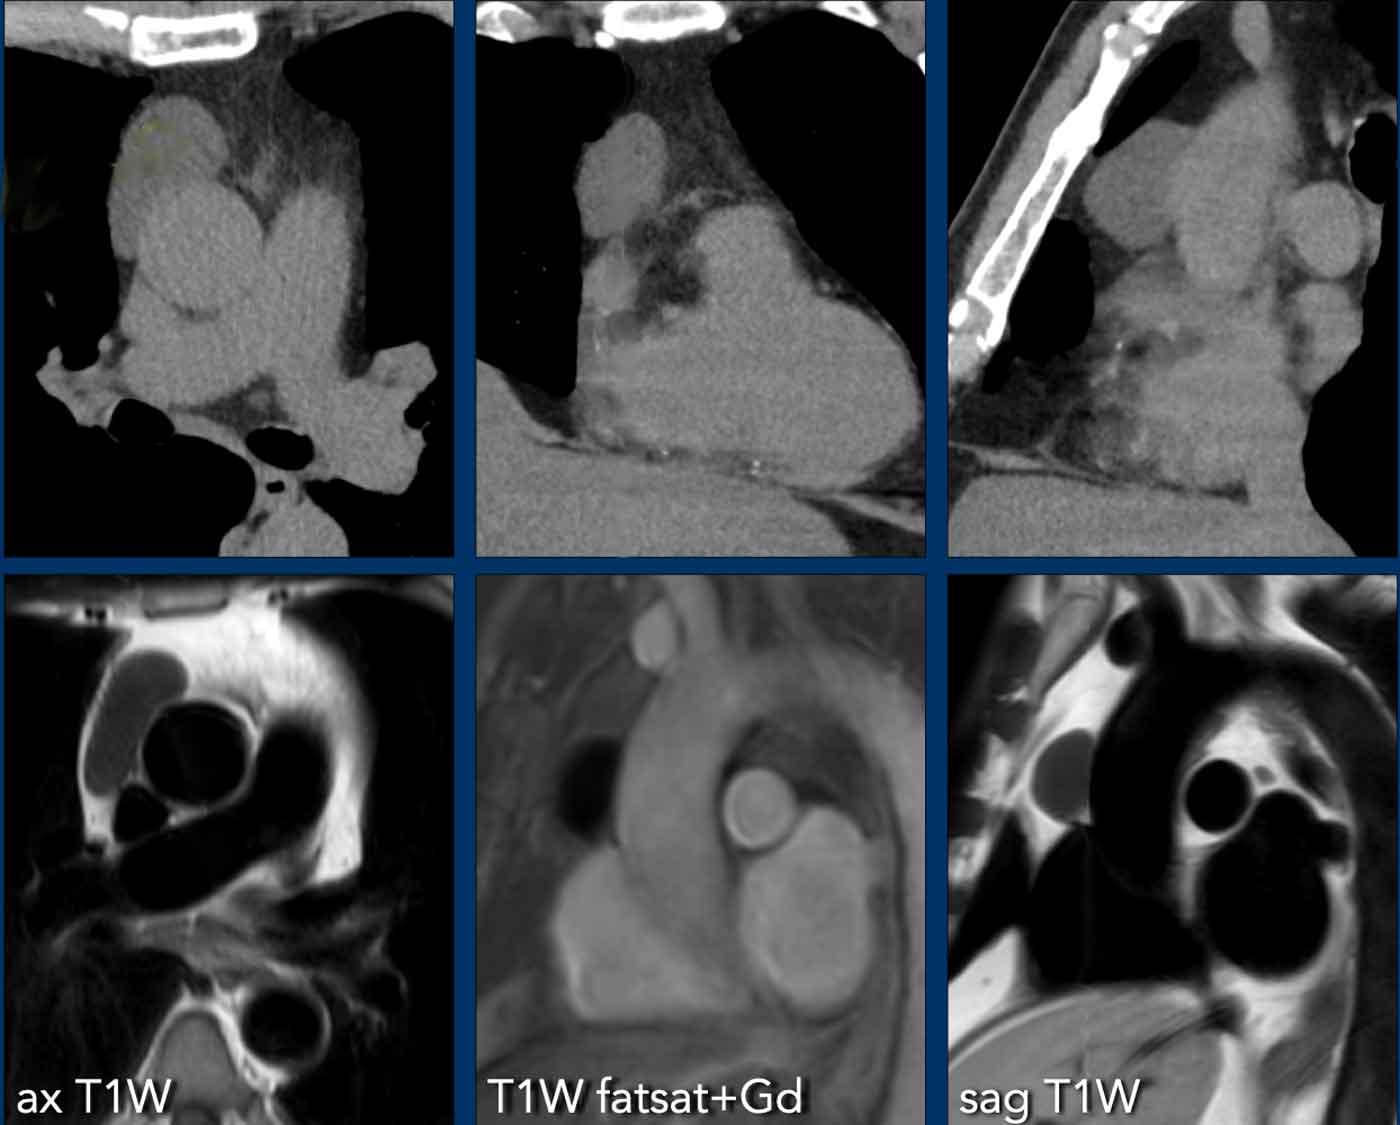

Các hình ảnh này của bệnh nhân nữ 28 tuổi.

Khối trung thất được phát hiện trên CT chụp để tìm thuyên tắc phổi.

Hình ảnh

Có một khối ở khoang trước mạch máu.

Có một số vôi hóa.

Tiếp tục với các hình ảnh MRI…

MRI thể hiện rõ hơn đây là tổn thương hỗn hợp với các thành phần dạng nang (chuỗi xung T2W) và các thành phần đặc có ngấm thuốc.

Không có hiện tượng giảm tín hiệu trên chuỗi xung T1W pha đối lập (out-of-phase).

Chẩn đoán cuối cùng

Kết quả cho thấy đây là u tuyến ức dạng nang.

Mặc dù hầu hết u tuyến ức biểu hiện là khối đặc hình bầu dục có ngấm thuốc, một số trường hợp có thể chứa các thành phần dạng nang và vôi hóa.

Điều này có thể gây khó khăn đáng kể trong việc phân biệt với u quái (teratoma).